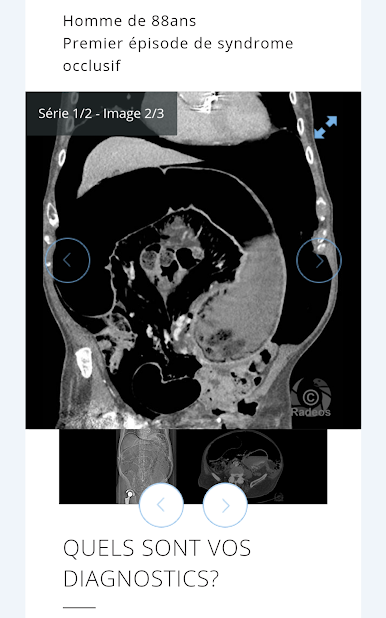

The largest French bank of clinical cases of medical imaging and radiology in your pocket!

Consultation with images of hundreds of typical and rare cases is simple, all accompanied by explanatory captions and course records. All imaging modalities are represented: CT, MRI, ultrasound, PET-CT scans, interventional radiology angiography.